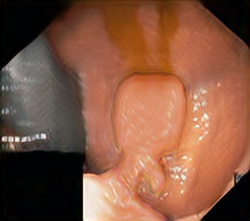

A few sample images and the corresponding masks of the polyp dataset in HyperKvasir are shown in Fig 2. The polyp images are RGB images. The masks of the polyp images are single-channel images with white () for true pixels, which represent polyp regions, and black () for false pixels, which represent clean colon or background regions. In this dataset, there are different sizes of polyps. The distribution of polyp sizes as a percentage of the full image size is presented in the histogram plot in Fig 3, and we can observe that there are more relatively small polyps compared to larger polyps. Additionally, a subset of this dataset was used to prove that the performance of segmentation models trained with small datasets can be improved using our SinGAN-Seg pipeline, and the whole dataset was used to show the effect of using SinGAN-Seg generated synthetic images instead of a large dataset which has enough data to train segmentation models. In this regard, this dataset was used for two purposes: